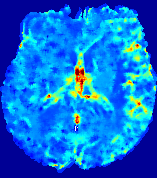

LesionRefer to captionRefer to captionRefer to captionRefer to captionRefer to captionRefer to caption𝐕rgbsubscript𝐕𝑟𝑔𝑏{\bf{V}}_{rgb}Refer to captionRefer to captionRefer to captionRefer to captionRefer to captionRefer to caption𝐕2subscriptnorm𝐕2{\|\bf{V}}\|_{2}Refer to captionRefer to captionRefer to captionRefer to captionRefer to captionRefer to captionRefer to caption3.53.53.52.82.82.82.12.12.11.41.41.40.70.70.70.00.00.0(mm/s)𝑚𝑚𝑠(mm/s)D𝐷DRefer to captionRefer to captionRefer to captionRefer to captionRefer to captionRefer to captionRefer to caption0.0200.0200.0200.0160.0160.0160.0120.0120.0120.0080.0080.0080.0040.0040.0040.0000.0000.000(mm2/s)𝑚superscript𝑚2𝑠(mm^{2}/s)Slice #1Slice #2Slice #3Slice #4Slice #5Slice #6

Figure 3: PIANO feature maps for one stroke patient, where the lesion is located in the left hemisphere. Top row: segmented stroke lesion region (white) on different slices, obtained from ISLES 2017. The corresponding slices for the PIANO feature maps are shown in the following rows.

For a better insight into an estimated velocity field 𝐕𝐕{\bf{V}} and diffusion field 𝐃𝐃{\bf{D}}, we compute the following maps: (1) 𝐕rgbsubscript𝐕𝑟𝑔𝑏{\bf{V}}_{rgb}: Color-coded orientation map of 𝐕=(Vx,Vy,Vz)T𝐕superscriptsuperscript𝑉𝑥superscript𝑉𝑦superscript𝑉𝑧𝑇{\bf{V}}=(V^{x},V^{y},V^{z})^{T}, obtained by normalizing 𝐕𝐕{\bf{V}} to unit length and mapping its 3 components to red, green, blue respectively; (2) 𝐕2subscriptnorm𝐕2\|{\bf{V}}\|_{2}: 222 norm of 𝐕𝐕{\bf{V}}; (3) D𝐷D: scalar field in Eq. 5.

Fig. 3 and Fig. 4 show the PIANO feature maps estimated from two ISLES 2017 patients: all are highly consistent with the lesion in both cases. Details of the blood flow trajectories are revealed in 𝐕rgbsubscript𝐕𝑟𝑔𝑏{\bf{V}}_{rgb} by the ridged patterns and the sharp changes of colors in the unaffected (right) hemisphere, while the flat patterns appearing within the lesion provide little directional information about the velocity and indicate low velocity magnitudes. Velocity magnitudes are more directly visualized via 𝐕2subscriptnorm𝐕2\|{\bf{V}}\|_{2}, from which one can easily locate the lesion where 𝐕2subscriptnorm𝐕2\|{\bf{V}}\|_{2} is low. D𝐷D also indicates lower diffusion values in the lesion, though with less contrast potentially due to the fact that it captures the accumulated effect of CA diffusion at the voxel-level.